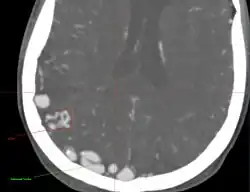

• Originally described by Luschka and Virchow in the mid-1800s, AVMs are abnormal communications between arteries and veins without the normal capillary flow.

• Abnormal communication between artery and vein, with disproportionate and unbalanced hydrodynamic stress across them. The direct connection between the arterial and venous systems exposes the venous system to abnormally high pressures and results in the formation of enlarged feeding vessels and enlarged draining venous structures.

• Point of abnormal communication is known as the nidus